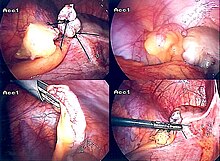

The surgical procedure for the removal of the appendix is called an appendectomy. Appendectomy can be performed through open or laparoscopic surgery. Laparoscopic appendectomy has several advantages over open appendectomy as an intervention for acute appendicitis.[72]

Laparoscopic appendectomy has become an increasingly prevalent intervention for acute appendicitis since its introduction in 1983.[76] This surgical procedure consists of making three to four incisions in the abdomen, each 0.25 to 0.5 inches (6.4 to 12.7 mm) long. This type of appendectomy is made by inserting a special surgical tool called a laparoscope into one of the incisions. The laparoscope is connected to a monitor outside the person's body, and it is designed to help the surgeon to inspect the infected area in the abdomen. The other two incisions are made for the specific removal of the appendix by using surgical instruments. Laparoscopic surgery requires general anesthesia, and it can last up to two hours. Laparoscopic appendectomy has several advantages over open appendectomy, including a shorter post-operative recovery, less post-operative pain, and lower superficial surgical site infection rate. However, the occurrence of an intra-abdominal abscess is almost three times more prevalent in laparoscopic appendectomy than open appendectomy.[77]